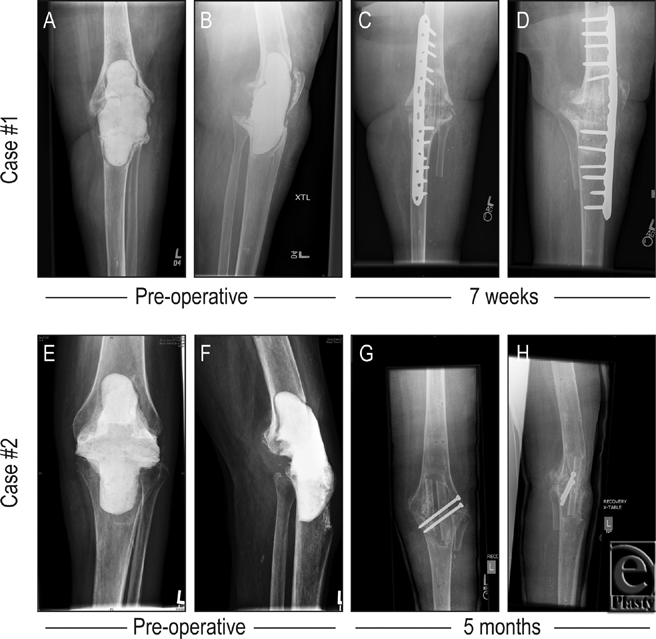

The procedure detailed earlier was performed with minor variation. Attempts at apposing the femur and tibia resulted in a 6-cm gap anteriorly. These bones were fixed with an anteromedial plate, and a combination of cortical and locking screws were placed. Demineralized bone matrix (DBX, Synthes) was applied to the gap posteriorly. The fibular flap was prepared by dividing the bone into a double barrel strut with maintenance of the periosteal blood supply to each half. An additional 6-cm bone was harvested from the fibula as a free graft and used as an additional fitted strut into the medial aspect of the knee arthrodesis. See Figures 1 and 2 for photographic and radiographic documentation. The patient was seen 1 year after arthrodesis, with the knee solidly fused in position. At that point was mobilized to pivot and transfer to and from her wheelchair on her on one remaining leg.

The procedure detailed earlier was performed with minor variation. The exposed femur and tibia were apposed with good bony contact, achieved posteriorly with alignment of the knee into a slightly valgus and flexed position. Two lag screws were placed from lateral to medial, stabilizing the bones initially, and external fixation was placed anteromedially. Fixation was performed to allow placement of the fibular graft anteriorly. The harvested fibula flap was prepared as a single vascularized strut. Postoperatively, the external fixation was removed after 4 months and the limb casted. Vancomycin was given for 6 weeks intravenously. This patient was evaluated in clinic 12 months postoperatively, with her knee solidly fused. She was able to ambulate with minimal assistance without pain at her arthrodesis site. See Figure 2 for radiographic documentation of these cases.

Slightly different fixation methods and flap utilization were employed in each case. In case 1, bone apposition of the host bone ends was marginal. An internal fixation bridging plate was placed anteromedially and bone graft was used to supplement the fixation. This was the best way to achieve good immediate stability and withstand the bending and torsional forces at the fusion site. In case 2, we were able to achieve good bone-to-bone apposition posteriorly, so we used interfragmentary compression screws posteriorly for internal fixation. We then used an external fixation device to supplement this method of fixation, as the screws alone were not sufficient to withstand the forces mentioned earlier, and plate fixation would not have allowed sufficient access to the defect for grafting.

In case 1, a double barrel strut configuration was used, while in case 2, the flap was not sectioned. Double strut utilization has an uninterrupted viable vascular supply across the periosteum21 and can be used to fill defects when a larger volume flap is required.22 Also in this case, an additional free fibular graft was available and was used to augment the construct. Therefore, the flap and fixation were tailored to the unique geometry of either defect.